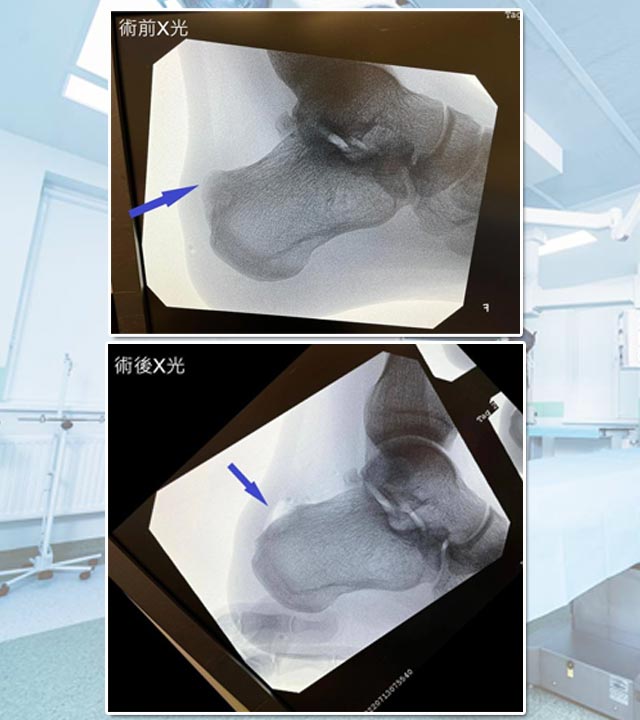

跟骨後上突增生-Haglund’s Deformity

病人最終在X光檢查下,發現後腳跟位置先天骨頭增生突出,症狀學名為。由於先天骨頭形狀;再加上後天因素,長時間跳躍、行路、站立等動作,漸漸後腳跟骨增生與阿基里斯跟腱形成重覆磨擦,因而誘發腫脹發炎。

以手術方法將骨增生移除及磨平,只要將摩擦阿基里斯跟腱的骨刺移除,就能大大改善症狀。

除了將骨增生移除,阿基里斯跟腱的缺口也需要作修復及強化,術後需要以特製鞋子保護跟腱約4-6星期。